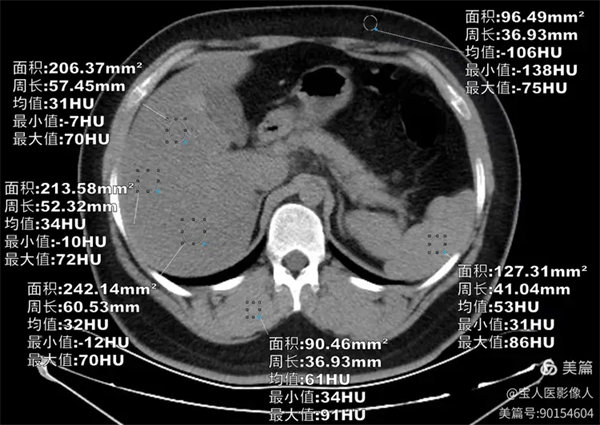

圖1

CT軸位,肝形態(tài),大小正常,CT值最低約31HU,較正常肝實質(zhì)密度降低。

PDFF測值,測量全肝實質(zhì)多部位的脂肪分?jǐn)?shù)值12%—17%,提示:脂肪肝,MR-PDFF,二級,中度。